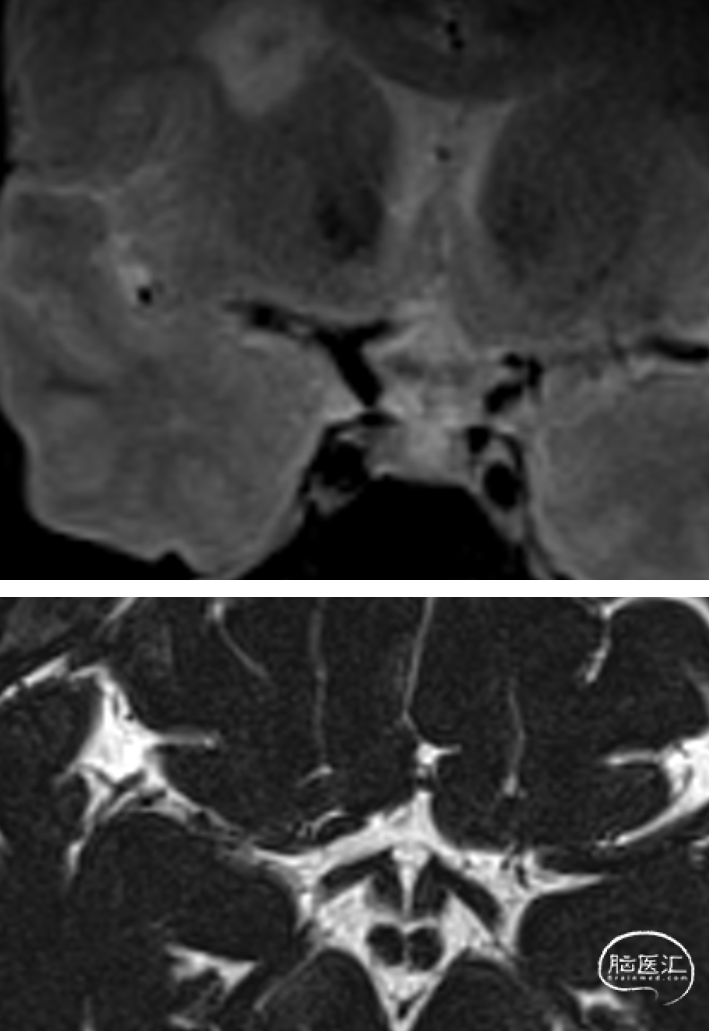

MR提示:右侧半卵圆区新发脑梗死(A、B)。

头颅CTA提示:右侧大脑中动脉M1段闭塞;左侧椎动脉V4段重度狭窄(C、D)

术前行高分辨率核磁共振:右侧大脑中动脉前壁强化斑块。